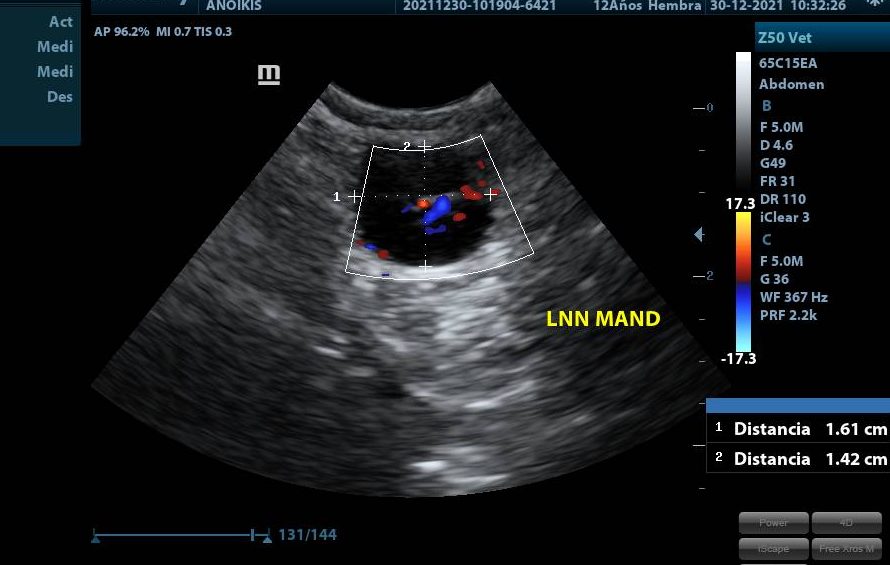

La ecografía en oncología ha evolucionado con los años y permite identificar el o los órganos afectados por la patología tumoral. Si bien esta técnica no permite conocer el diagnóstico final de la enfermedad, es una herramienta fundamental en la clínica oncológica diaria.

El modo B es el más utilizado y permite formar una imagen en tiempo real bidimensional. El Doppler color o power permite en diferentes escalas y precisión determinar el flujo sanguíneo y vascularización de una formación u órgano. Esta técnica es fundamental en oncología ya que en general las enfermedades tumorales malignas tienden a tener mayor vascularización que aquellas no tumorales o benignas. Además, nos permite asegurar una toma de muestra segura cuando se realizan punciones ecoguiadas evitando estructuras altamente vascularizadas.